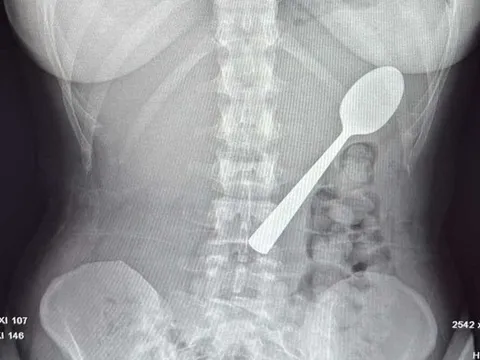

Bé trai 13 tuổi chảy máu nhiều, bác sĩ sốc khi phát hiện bí mật "đáng sợ" ở cổ - Ảnh 3.Đau quặn bụng dữ dội, người phụ nữ 55 tuổi phát hiện bí mật đáng sợĐỌC NGAY